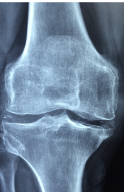

다리 관절 부위에 뻣뻣함과 제한된 움직임이 있는 경우, 퇴행성 관절염이나 골다공증의 가능성이 있습니다. 퇴행성 관절염은 연령이나 과부하 등에 의해 관절의 연골이 손상되어 발생하는 질환으로, 무릎관절염, 고관절염 등이 있습니다. 골다공증은 성별이나 호르몬 변화 등에 의해 뼈의 밀도가 감소하여 발생하는 질환으로, 골반골절, 척추골절 등이 있습니다. 이러한 경우에는 칼슘제나 비스포스포네이트 등의 약물 치료가 필요하며, 경우에 따라서는 수술이 필요할 수도 있습니다.

첫째, 골관절염입니다. 골관절염은 관절의 연골이 손상되어 관절에 염증이 생기는 질환입니다. 연골이 없어지면 뼈와 뼈가 마찰하게 되어 통증과 염증이 발생합니다. 골관절염은 나이가 들면서 자연스럽게 발생할 수 있으며, 비만, 외상, 유전 등이 위험 요인입니다.